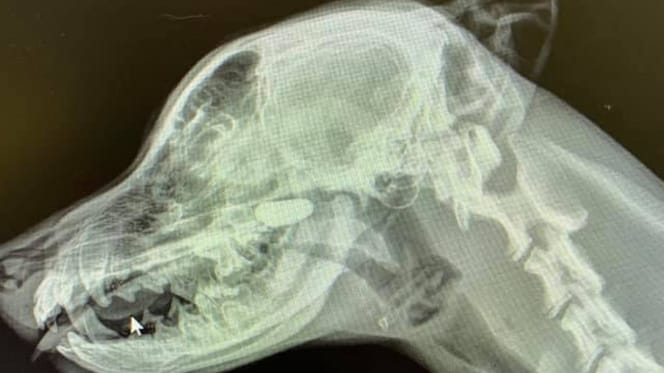

Zdjęcie rentgenowskie głowy psa

Widok zdjęcia rentgenowskiego wprawił wszystkich w osłupienie

© Sarah Yuki @Iloveveterinarymedicine / Facebook

Lekarka kontynuowała więc badania i zleciła wykonanie zdjęć rentgenowskich młodego psa. Najpierw klatki piersiowej, ale na tym zdjęciu Sara przy najlepszych chęciach nie mogła dostrzec niczego podejrzanego. Dlatego zleciła jeszcze prześwietlenie głowy i szyi z boku. I to okazało się strzałem w dziesiątkę!

W nosogardzieli wyraźnie widać ciało obce, którego absolutnie nie powinno tam być.

Okazało się, że to kamień, który szczeniak w jakiś sposób włożył sobie do nosa! Po jego usunięciu szczeniakowi od razu się poprawiło.